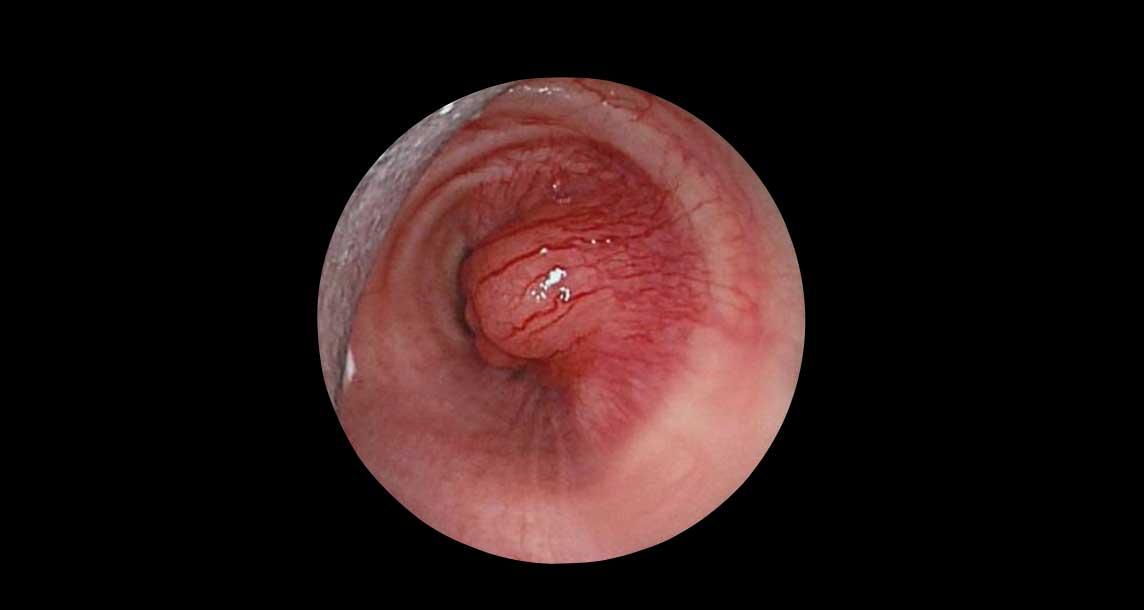

Tiếp tục xem hình ảnh nội soi phế quản…

Hình ảnh nội soi phế quản cho thấy hình ảnh điển hình của tổn thương bờ rõ, có mạch máu, gây tắc nghẽn lỗ vào thùy dưới.

Giải phẫu bệnh: U carcinoid.